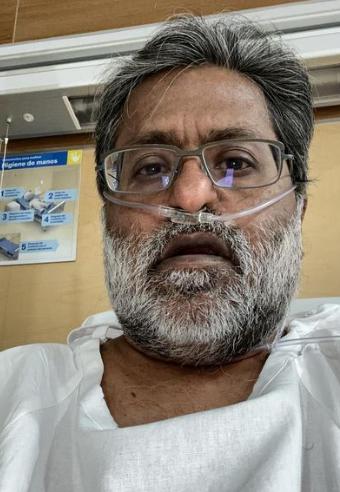

The Founder and Ex-Chairman of the Indian Premier League (IPL), Lalit Modi, informed everyone that he is currently on 24×7 oxygen support after he suffered from COVID-19 and severe pneumonia. The businessman shared the news on his Instagram handle after he received a lot of wishes for his speedy recovery. According to Lalit Modi’s Instagram post, he battled against COVID-19 for three weeks and after which he suffered major lung damage because of deep pneumonia and fought against it for the next two weeks.

On January 14, 2023, Lalit Modi took to his Instagram handle and shared a series of pictures featuring his multiple selfies and screengrabs of his medical reports. He also shared a picture of a fingertip pulse oximeter in which we can see the reading 87, which clearly shows how seriously low was his oxygen levels. Along with the pictures, Lalit Modi also penned a long note in the caption. In his note, he thanked his son, Ruchir Modi, for arranging everything to bring him back to London. His note can be read as:

“After 3 weeks in confinement with a double COVID in 2 weeks accompanied by influenza and deep pneumonia – and post trying several times to leave. Finally landed via air ambulance accompanied by two doctors and superstar super efficient son who did so much for me back in London. The flight was smooth. Unfortunately still on 24/7 external oxygen. Thank u to all at @vistajet for going the extra mile. I am extremely grateful to all. Love to all. Big hug.”